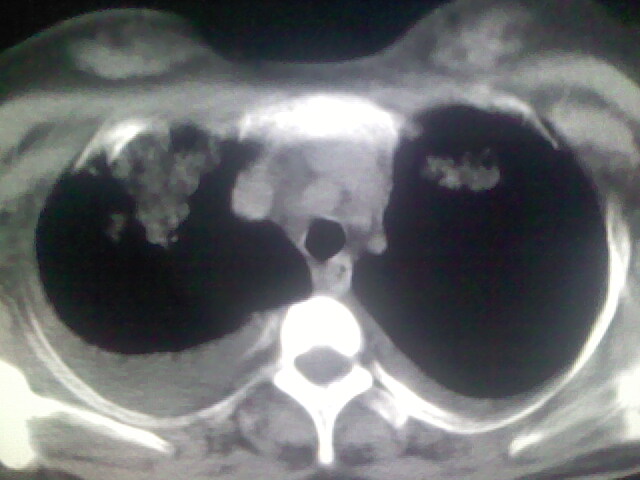

双肺“肺泡性肺水肿” “胸腔积液”!

双肺“肺泡性肺水肿” “胸腔积液”

考虑肺梗塞、肺水肿,双侧胸腔积液

考虑产后心肌病,心功能不全,肺水肿,双侧胸腔积液。不排除羊水栓塞可能。

双肺水肿,双侧胸腔积液,肺梗死不能排除